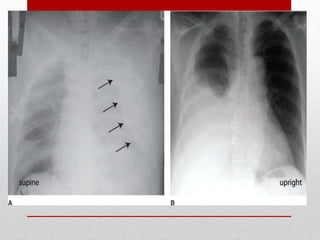

Hemothorax and

Pneumothorax - most

common injuries from both

blunt and penetrating

thoracic trauma